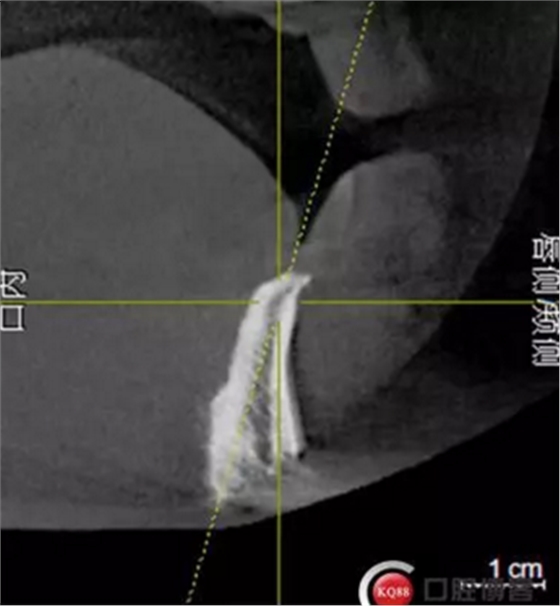

檢查:上頜無牙頜假牙穩(wěn)定性尚可,下頜3435364243殘根;33殘冠1-2度松動,其他牙齒缺失;CBCT檢查:下頜牙槽骨前牙區(qū)骨高度足,后牙區(qū)骨高度最低為8mm,骨寬度足。

1)術前檢查,拍攝臨床照片及CBCT檢查,制取活動義齒參考模型,指導后期最終修復的牙齒排列

2)術前準備及手術過程,測量血壓及血糖,簽種植知情同意書;嚴格遵循無菌操作,局麻下采用微創(chuàng)技術于323436分別植入osstem4.0X10,4.0X10,4.5X7; 434446分別植入osstem4.0X1O,4.0X10,4.5X7.初期穩(wěn)定性均達到了35N.CM以上;嚴密縫合,止血,種植體位點和方向與設計一致。